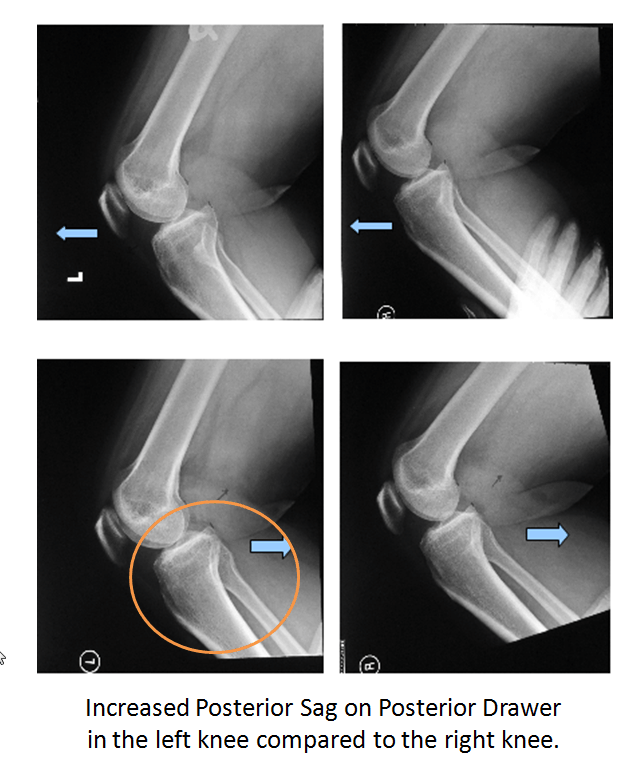

I find the stress views of the knee in the lateral position with the knee at 90 degrees of flexion useful. I will request that each knee be subjected to an anterior and posterior drawer at the time of the x-rays. The knee with the PCL tear will show increased posterior translation of the tibial with respect to the femur.

Note the increased posterior sag in the left knee compared to the right knee during posterior drawer test: